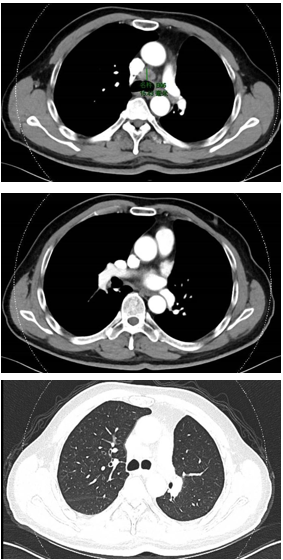

57岁男性患者,因“反复胸部不适,确诊为左肺上叶腺癌后经历多次治疗方案失败”入院。2020年4月,患者因胸部不适就诊,影像学检查发现左肺上叶占位性病变,同年6月在本院胸外科接受“胸腔镜下左肺上叶切除术+淋巴结清扫术”。术后病理诊断为左肺上叶浸润性腺癌(II-III级,腺泡+实体型),肿瘤大小1.5×1.2×1cm,未侵犯肺门及胸膜,支气管切缘未见肿瘤残留。免疫组化显示肿瘤细胞TTF-1(+)、Napsin A(+)、CK(+)、P63局灶(+)、P40(-)、CK5/6(-)、Syn(-)、CgA(-)、Ki67约40% (+)。基因检测发现EGFR 19号外显子非移码缺失突变(13.2%)、BRAF-TRIM24融合(12.4%)、SMARCA4 26号及9号外显子移码突变。PD-L1表达TPS为50%,PS评分为0。

术后辅助治疗(2020年7月):培美曲塞+卡铂化疗4周期,后改为埃克替尼靶向治疗。

复发及治疗调整(2021年4月):拒绝放疗,改用多西他赛联合奥希替尼治疗。

靶向联合治疗(2022年1月):曲美替尼+奥希替尼治疗,后因病情进展改为曲美替尼+达拉非尼+奥希替尼联合治疗,辅以胸腔药物灌注及热疗。

免疫联合化疗(2022年12月):紫杉醇+卡铂+PD-1抑制剂+贝伐珠单抗,共6周期。治疗后积液显著吸收,脑转移灶缩小。

维持治疗及随访(2023年6月至今):紫杉醇+PD-1抑制剂+贝伐珠单抗维持治疗。2025年6月MRD检测发现SMARCA4突变低丰度阳性,提示可能复发,需进一步评估。